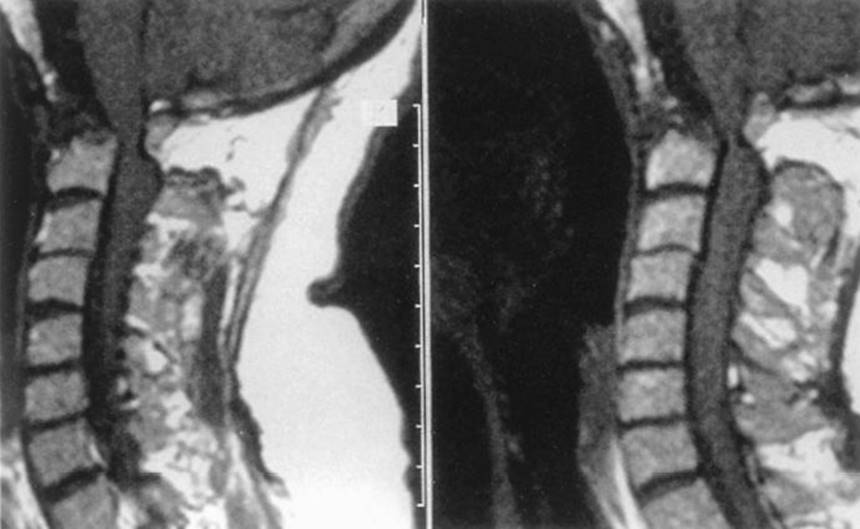

b. Radiographs. Plain X-rays and MRI scans are best for showing erosion of the odontoid process with subsequent instability (Fig. 22.5).

FIGURE 22.5 Left and right: Sagittal MRI scans in rheumatoid arthritis demonstrating destruction of the dens with compression of the medulla and spinal cord at the cranio-cervical junction.